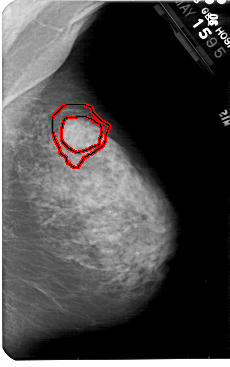

A_1823_1.RIGHT_MLO

LEFT_MLO LINES 5491 PIXELS_PER_LINE 3571 BITS_PER_PIXEL 12 RESOLUTION 43.5 NON_OVERLAY

FILE: A_1823_1.RIGHT_MLO.OVERLAY

TOTAL_ABNORMALITIES 1

ABNORMALITY 1

LESION_TYPE MASS SHAPE IRREGULAR MARGINS ILL_DEFINED

ASSESSMENT 4

SUBTLETY 4

PATHOLOGY MALIGNANT

TOTAL_OUTLINES 2

BOUNDARY

CORE